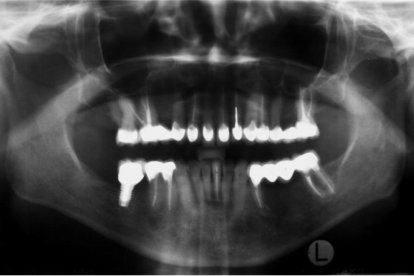

A las personas que sufren de bruxismo, los dentistas cuidan de que mantengan buena mordida y les colocan protector.

Los dentistas revisan que la oclusión (el alineamiento de los dientes y la forma como se ajustan, la mordida), esté buena, explica Gallardo.

Cuando una persona pierde una muela o un diente se rompe todo el equilibrio y eso da paso a que la mordida cambie. “Eso puede desencadenar en un problema articular, en un bruxismo, apretamiento”, indica.